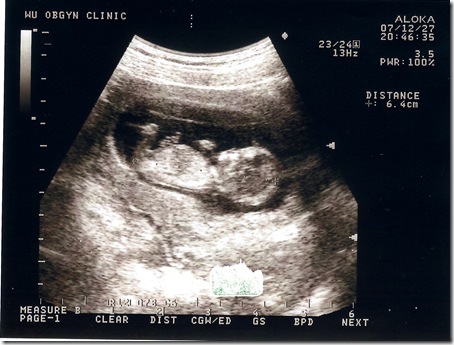

| 地點 | 12/28汐止吳婦產科 | 普通掛號, 超音波 |

| 週數 | 13週 | 這時你如果用手輕輕在腹部碰觸,胎兒就會蠕動起來,但你仍然感覺不到胎兒的動作。 胎兒的神經元迅速地增多,神經突觸形成,胎兒的條件反射能力加強,手指開始能與手掌握緊,腳趾與腳底也可以彎曲,眼瞼仍然緊緊地閉合。 |

| 身長 | 6.4cm | OK |

| 心跳 | 150下/分鐘 | OK |

這次的超音波就不用畫圖說故事了吧 !!

花了150塊就照了這一張超清楚的照片

醫生也細心地講解各部位的發育

小baby還一邊揮舞著小手 看起來也像是在吸手指..

從右邊的數據可以看到頭臀長己經有6.4公分了

嗯.. 不錯

有乖乖在長大